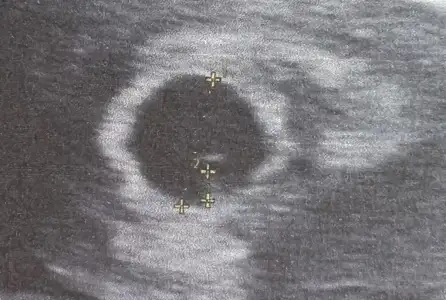

Evet araştırdım şimdi netten pelvik ağrı diye geçiyormuş hamilelikte oluyormuş zaten en azından normal bir durummuş :)Normal bence rahim büyüyo bebek büyüyor. Benim bel ağrım var başından beri geçmiyo o degıl daha yeniyiz göbek şiştikce bel boşlugu oluşacak daha çok agrıyacak.

İçin rahat olsun doktoruna da danısırsın gıdınce